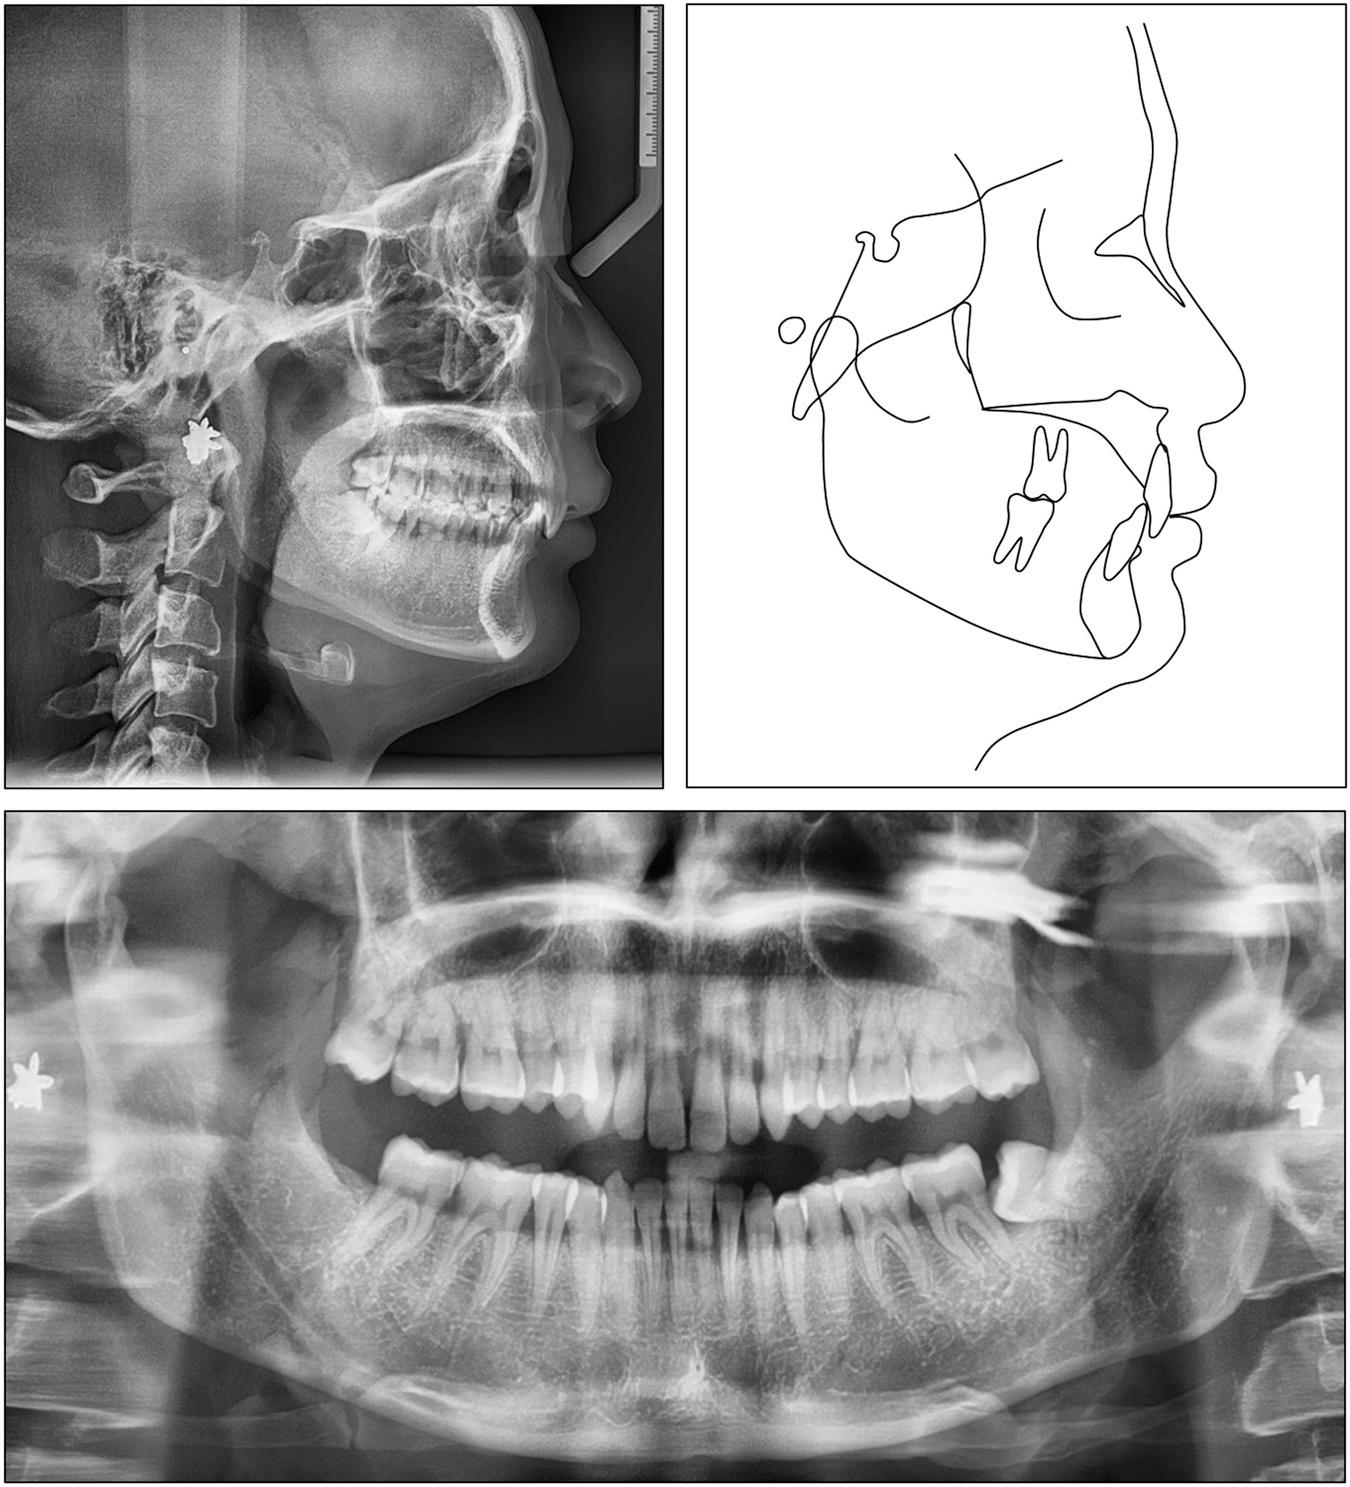

The lateral cephalometric analysis revealed a skeletal Class II relationship with a normally positioned mandible and a protruded maxilla (SNA: 85.7°, SNB: 79.6°, ANB: 6.1°). The vertical skeletal pattern was hypodivergent (FMA: 20.0°). The upper incisors were severely retroclined (U1/SN: 80.3°) while the lower incisors were slightly proclined (IMPA: 94.2°). The upper incisal display was large (5.8 mm). The upper and lower lips were normally placed (upper lip to E-line, -0.7 mm; lower lip to E-line, -1.2 mm) (Table I). The panoramic radiograph showed the presence of all teeth except the mandibular right third molar (Figure 2).

Case 1: initial panoramic and cephalometric radiographs and tracing.